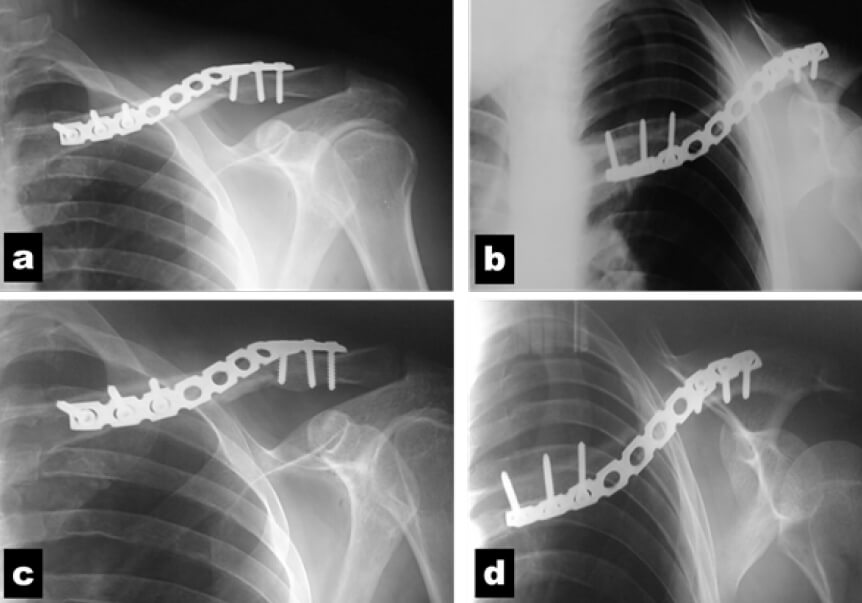

Figura 5. Resultados radiológicos en proyecciones anteroposterior y axial (Clavícula en “S”): a y b: 8 semanas de post operatorio. c y d: 12 semanas de post operatorio.

El paciente se le indicó el uso de un cabestrillo durante 7 días el cual fue retirado en su primera consulta post-operatoria. Se aplicaron los cuestionarios para la evaluación clínica y se realizaron controles radiográficos (proyecciones anteroposterior y axial de clavícula) en las consultas control a los 2, 4, 8, 12 y 16 semanas.

El puntaje de acuerdo al cuestionario QuickDASH fue 47,7 a las 4 semanas del post operatorio, 25 a las 8 semanas y 2,3 a las 12. El paciente reportó puntaje de 2 en la EVA para la 4 semana, de 1 para la 8va y 0 para las 12. Con respecto a la Escala de Constant-Murley, el puntaje fue de 46 a las 4 semanas, 14 a las 8 y 4 a las 12 semanas (al compararlo con el hombro sano).

Se encontró consolidación Montoya III a las 08 semanas del post-operatorio, y en el mismo momento el paciente se reincorporó a sus actividades laborales y cotidianas regulares sin restricciones. Para su consulta de las 12 semanas se evidenció consolidación de la fractura Montoya IV (Figura 6)